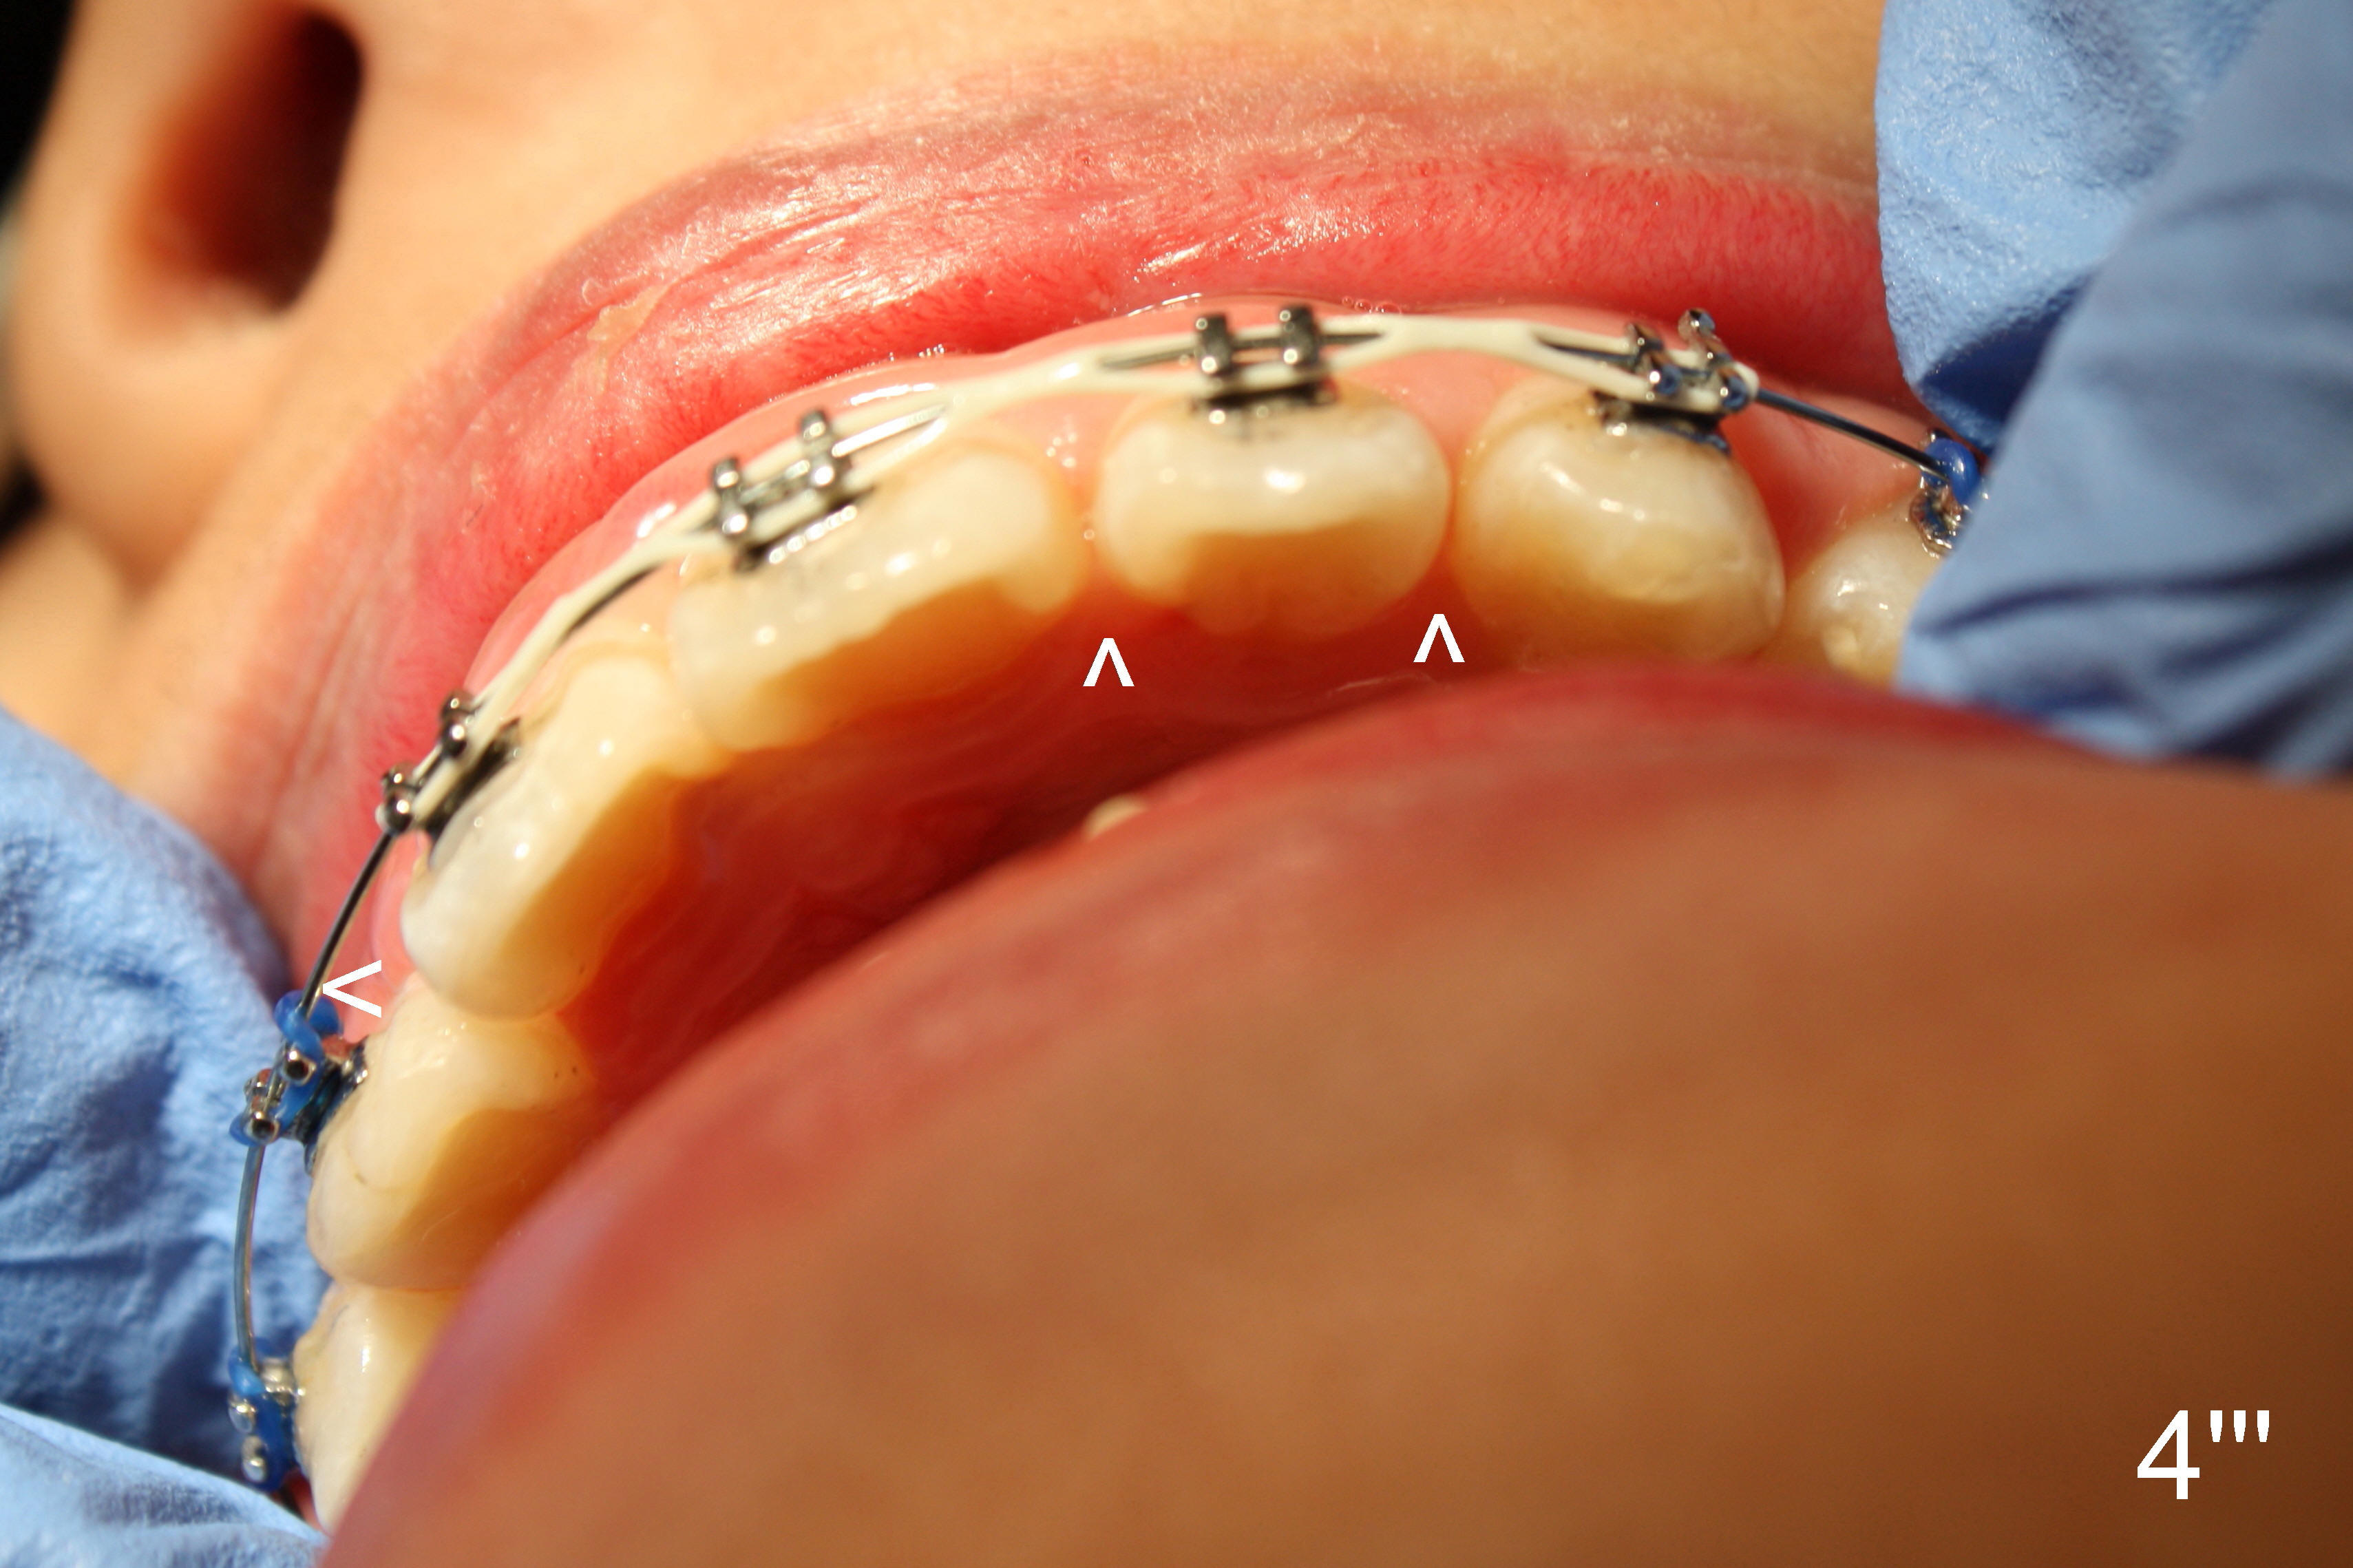

| Fig.4: Immediately post banding and bracketing, .012 niti | Fig.4': One month post banding and bracketing, .014 niti |

In fact, the patient returned earlier, because UL 5 bracket was loose. There were still spaces among UL 1-3 (Fig.4''': ^). The arch wire did not engage completely into the mesial slot of UR2 bracket (<). Therefore, power chains were placed among UR1-UL3 using the latter as an anchorage. It is hoped that UR2 will get extra space mesially for rotation correction.